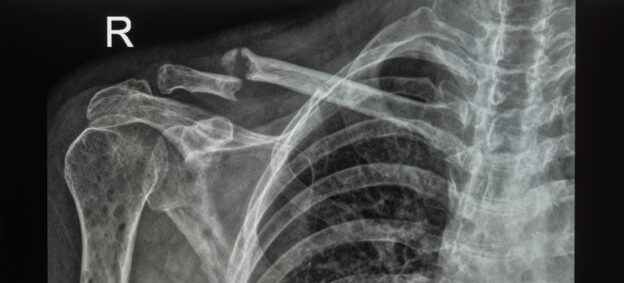

Mnohočetný myelom je nemoc známá již od 2. poloviny 19. století. Jedná se o nádorové onemocnění pocházející z krevních buněk zodpovědných za naši imunitu. Jde o jeden typ bílých krvinek, které jsou dominantně zodpovědné za tvorbu protilátek, tedy za naši imunitu. Tyto nádorově změněné plazmatické buňky však produkují vadnou protilátku, kterou nazýváme paraprotein. Ten ztrácí svoji schopnost bránit rozvoji infekce, a navíc může vážně poškozovat ledviny. Dále tyto nádorově změněné plazmatické buňky produkují speciální působky vedoucí k poruše kostní přestavby (zvýšenému odbourávání kostní hmoty – osteolýze) s tvorbou ložisek („děr“) v kostech a k jejich následným zlomeninám, projevujícím se v případě postižení obratlů bolestmi v zádech. Odtud pramení zlidovělý název „kostižer“.

Může tomu nějak napomoci i sám pacient? Toto je velmi složitá věc, protože nechceme v naší populaci vytvářet paniku. Nejčastějším prvním projevem jsou stupňující se bolesti zad při postižení obratlů s jejich kompresivními zlomeninami. Koho však v seniorském věku nebolí záda, že? Nemůžeme se ani moc opřít o rodinnou anamnézu, protože zde nebyla prokázána dědičnost. Nejedná se ani o nakažlivé onemocnění.

Diagnóza se opírá o rtg. snímek bolestivé oblasti a vyšetření krve. Definitivní diagnózu potvrdí vyšetření kostní dřeně. Typickou známkou MM je tvorba tzv. paraproteinu zachytitelného v krvi, na což může upozornit vysoká hodnota celkové bílkoviny v biochemickém vyšetření krve. Proto apelujeme na pravidelné preventivní prohlídky se základním krevním vyšetřením, které dokáží u velké části nemocných vést k vyslovení podezření na MM. Myelom sice postihuje spíše starší populaci, nicméně se může objevit i u lidí ve věku kolem 40–50 let, proto by se pravidelné prohlídky měly týkat již lidí od 40 let. Zejména u nemocného se zhoršujícími se bolestmi zad trvajícími déle než měsíc jsou proto kromě rtg. snímku doporučovány základní krevní testy u praktického lékaře cílené na tuto nemoc.